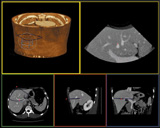

(株)AZEは,Virtual Placeシリーズのオプションとして,新ソフトウエア「疑似超音波(CTUS)」と「マルチアングル・マルチスライス」の2種を発売した。「疑似超音波」は,CT画像を再構成することで,擬似的に超音波画像をつくるソフト。通常の超音波画像よりも空間分解能に優れ,空気の影響を受けないため細部まで認識しやすい画像が得られる。位置関係の把握が容易で,教育用としての実用性も期待できる。一方の「マルチアングル・マルチスライス」は,曲がった腰椎など角度を認識して,自動的に直交断面を探して平面画像として表示。椎体のCT検査での画像処理時間の削減を実現する。